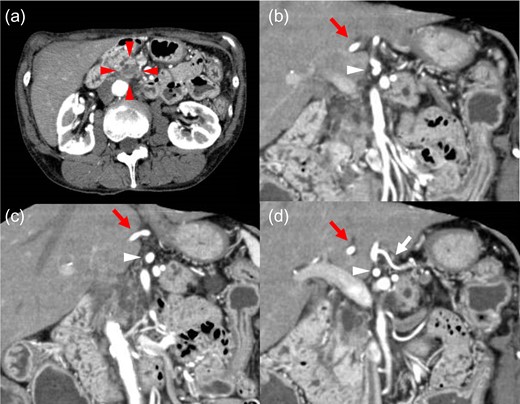

A 67-year-old woman with a 1-month history of epigastric pain was referred to our hospital with suspected pancreatic head cancer. Endoscopic ultrasonography and fine-needle biopsy of the tumor revealed adenocarcinoma of the pancreatic head. Computed tomography (CT) showed a 17 × 12 mm hypovascular tumor without arterial or portal venous invasion in the pancreatic head, and the CHA formed a common trunk with the LGA, coursing within the lesser omentum (Fig. 1). In addition, preoperative three-dimensional CT angiography revealed that the celiac artery branched into the splenic artery and the common trunk, and the usual CHA was absent in the supra-pancreatic area. The CHA formed a common trunk with the LGA and arched in a cranial direction within the lesser omentum immediately adjacent to the liver. No other arterial supply to the liver was identified (Fig. 2). With the preoperative diagnosis of resectable pancreatic head cancer and clinical staging of T2N0M0 (UICC 8th edition), pancreatoduodenectomy was planned.

Axial and reconstructed coronal contrast-enhanced CT. (a) Axial contrast CT image showing a 17 × 12 mm hypovascular tumor in the pancreatic head (red arrowhead). No enlarged lymph nodes or distant metastases were detected. (b–d) Coronal contrast CT image showing the CHA (red arrow) forming a common trunk (white arrowhead) with the LGA (white arrow) and coursing within the lesser omentum. CHA: common hepatic artery. LGA: left gastric artery.